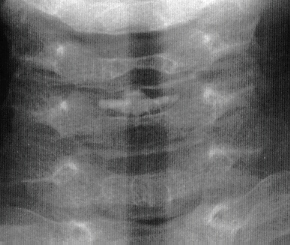

The patient is a 4 year old male who developed an insidious onset of

neck pain and stiffness 4 days prior to admission. Over the intervening

period, the patient suffered from worsening of his symptoms which led to

increasing irritability and difficulty sleeping. On the day of admission,

he developed severe neck pain. It was observed that his head was in a fixed

position just slightly right of midline. The patient's past medical history

was remarkable for two recent self-limited episodes of hives and urticaria

on his trunk and extremities that was treated with prednisone. There was

vague history of remote trauma about one month previously when the patient

had been "horsing" around with his brother. The child had no

evidence of a viral prodrome, constitutional symptoms or travel history.

The

anatomic location of this calcification is in the nucleus pulposus.